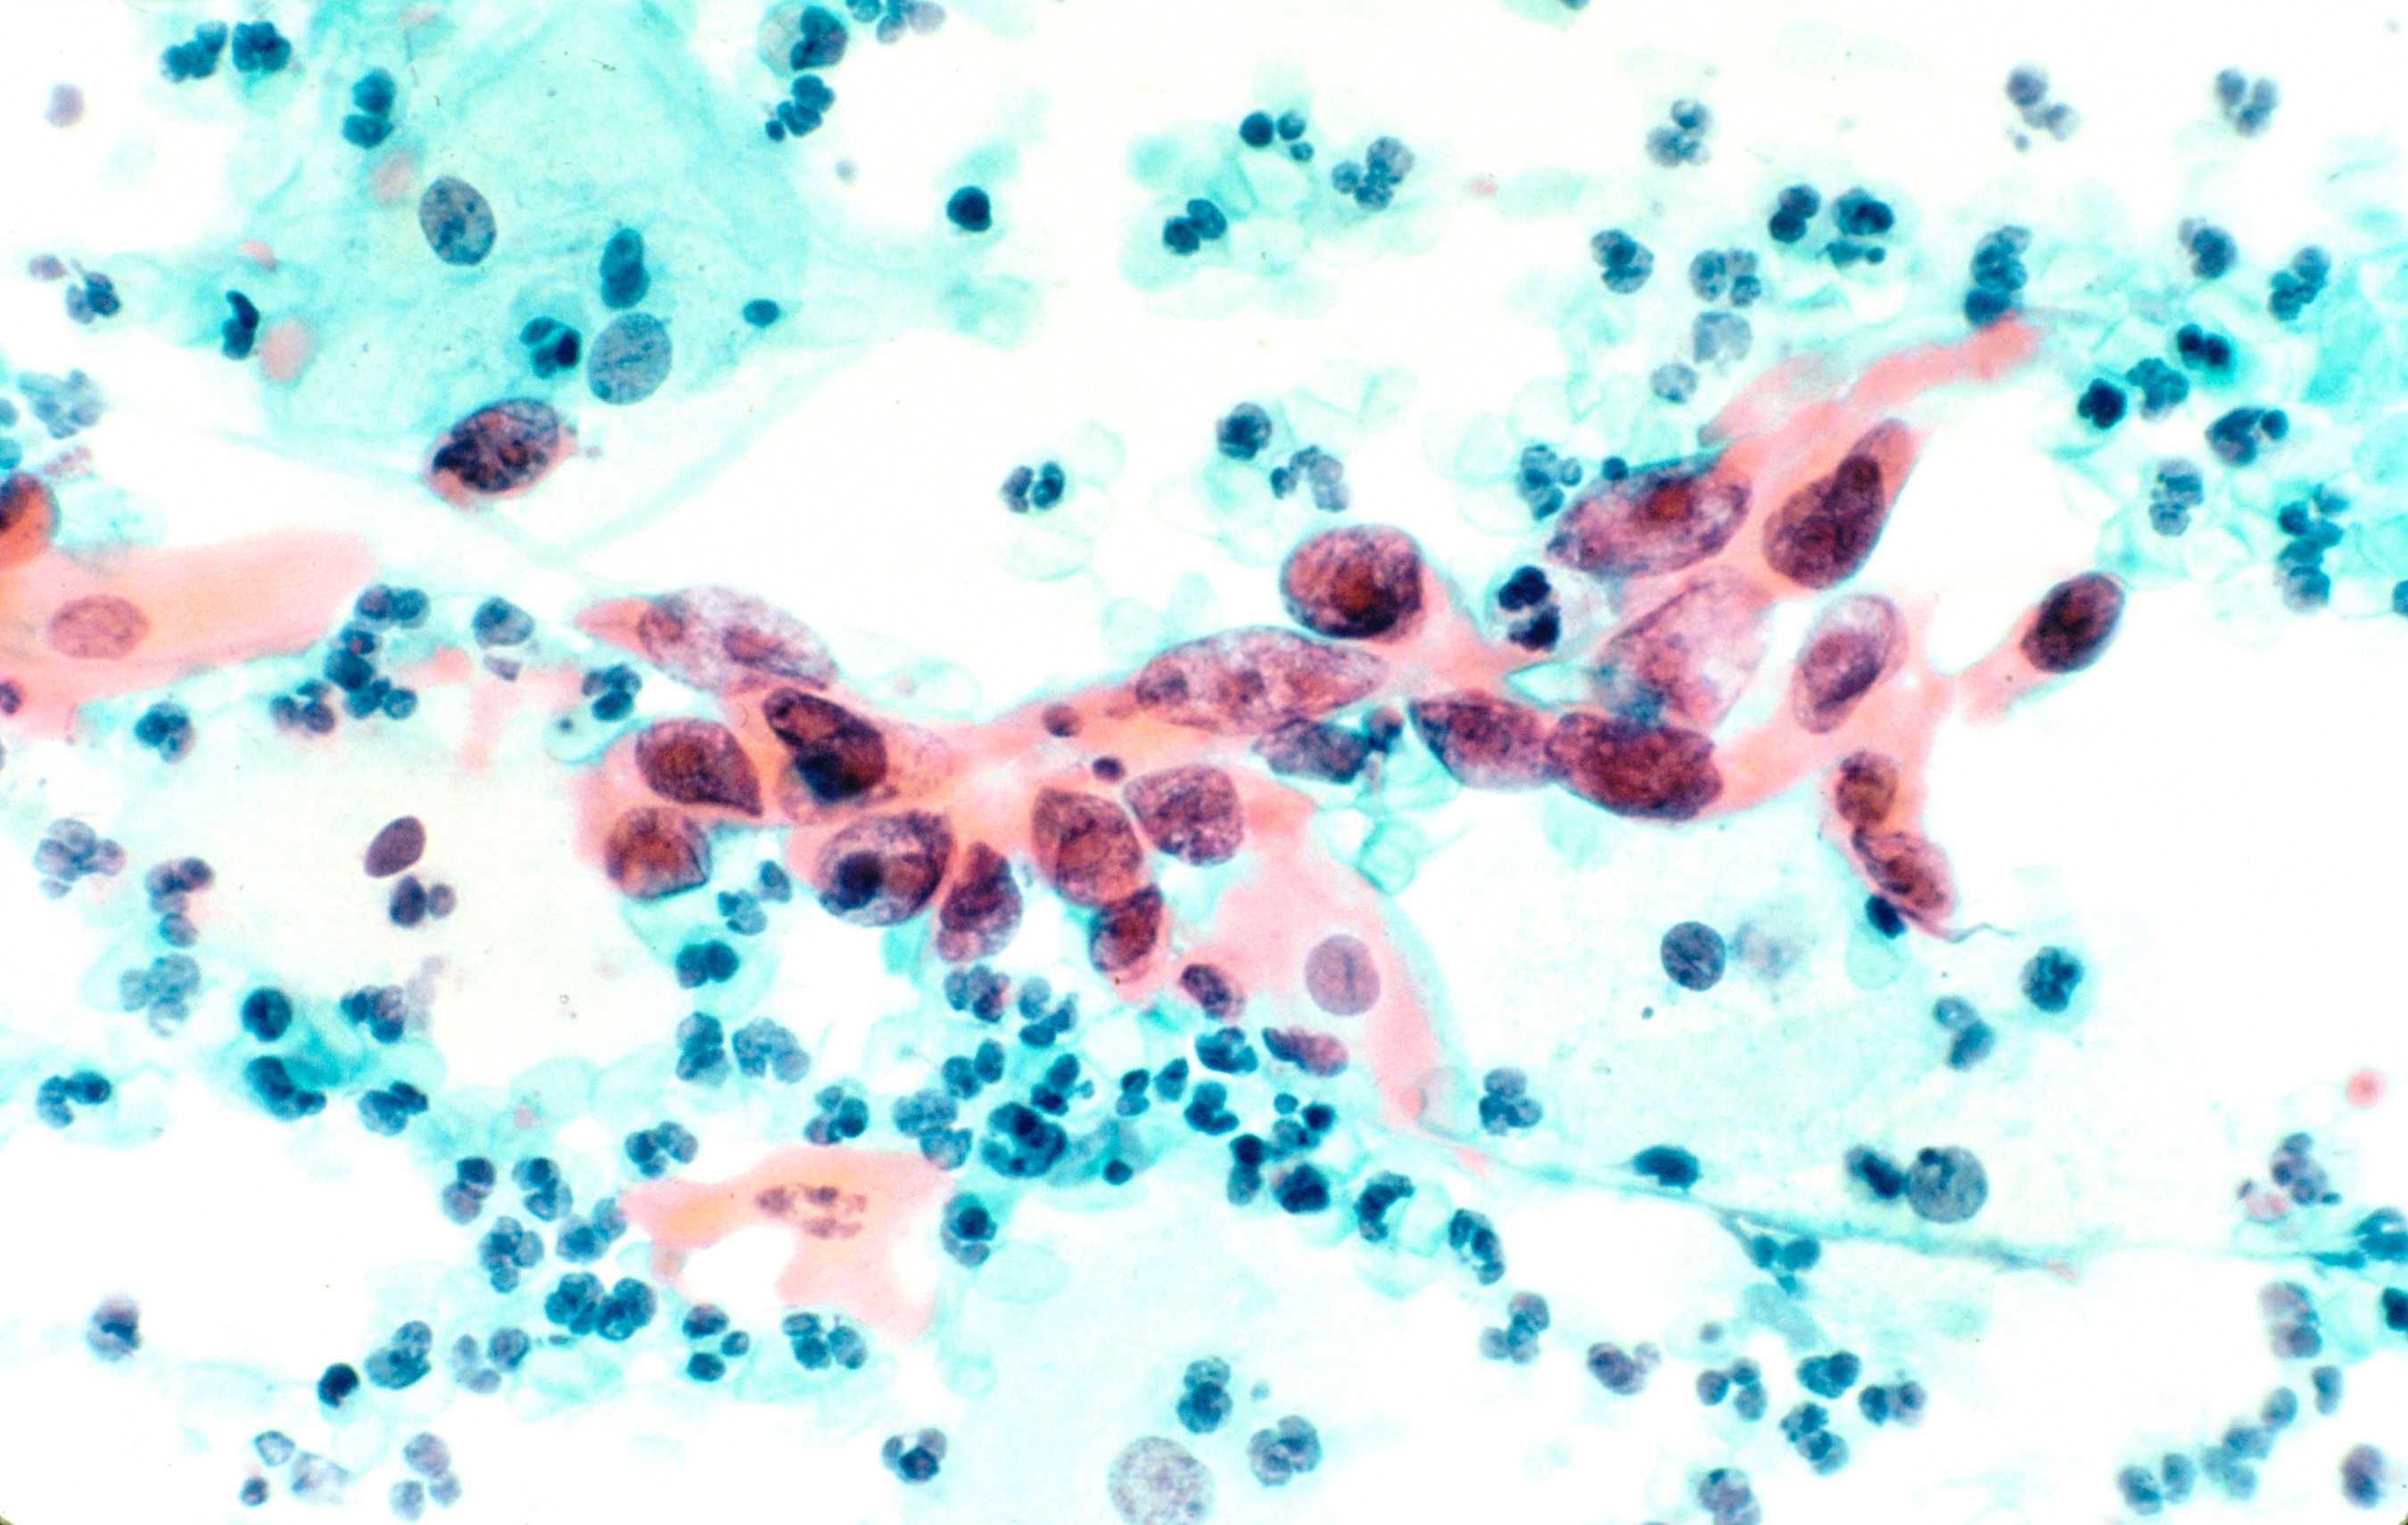

42+ Hpv Positive And Abnormal Pap Pictures. Positive pap and hpv tests are markers of early signs of cervical cancer, which often does not cause symptoms until it is advanced. N lgsil (low grade squamous intraepithelial lesion).

Self Sampling Hpv Test In Women Not Undergoing Pap Smear For More Than 5 Years And Factors Associated With Under Screening In Taiwan Sciencedirect from ars.els-cdn.com Recent studies show that hpv can spontaneously disappear with time. N hpv (human papilloma virus). An abnormal pap smear doesn't even necessarily hint at you having precancerous cells.